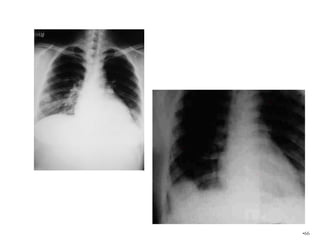

 Blood : The main method of spread ,and

occurs to;

 Genital : Vagina, vulva, and ovary.

 Extra genital : Lung, liver, brain, and

bones especially skull and spine.

 The lung is the commonest site for

secondaries and haemoptysis may be the

presenting symptom.

 Investigation:

 Serum hCG.

 Chest X-ray for pulmonary metastasis.